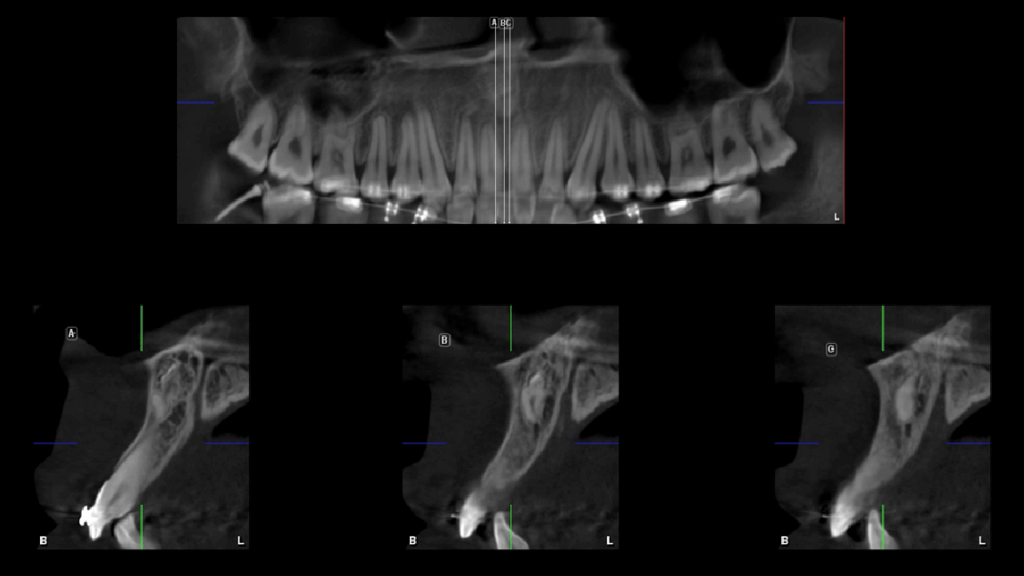

En la radiografía panorámica (Figura 1), se aprecia imagen radiopaca proyectada sobre línea media.

Radiografia Panorámica

caso 328 idm raciografia panoramica